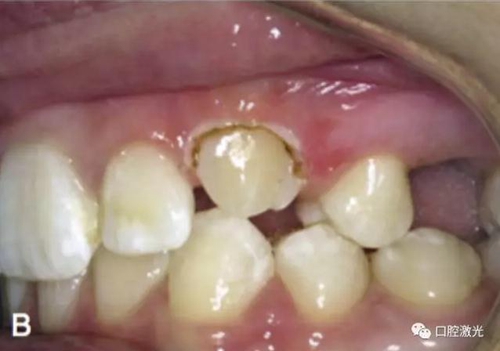

激光牙齦切割后即刻

在近似理想位置粘接托槽

治療前

粘接托槽